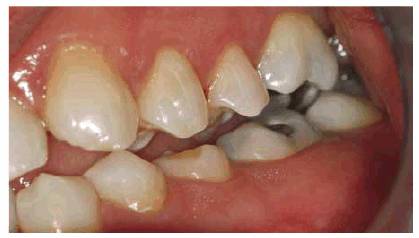

patient (Figures 17-1A to

C

Figure 17-1A to C: These photographs illustrate the complex dental condition of a 71-year-old male: (A) The palatal cervical regions of the maxillary anterior teeth exhibit sharp, wedge-like lesions that are characteristic of abfraction. These areas would be difficult, if not impossible, to have resulted from toothbrush abrasion. (B) The buccal aspects of the maxillary posterior teeth show smooth, concave configurations that are consistent with toothbrush abrasion and/or erosion. (C) The buccal surfaces of the mandibular teeth have lesions that possess components of both abfraction (sharp margins in the occlusal regions) and abrasion (concave geometry and gingival recession in the cervical regions).